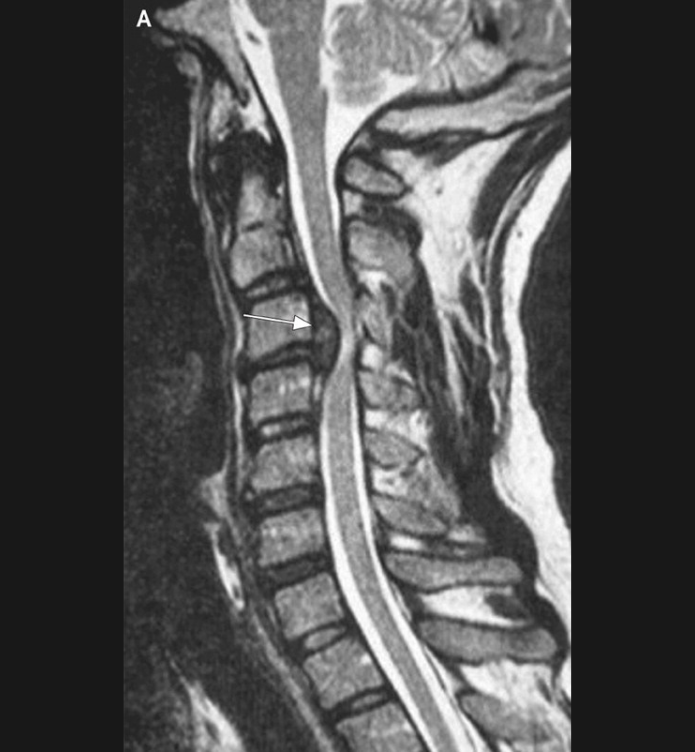

Basit Omurga ve Omurilik Anatomisi Omurga, 33 adet omur kemiğinden oluşur. Bu kemiklerin 7 tanesi boyun omuru, 12 tanesi sırt omuru, 5 tanesi bel omurudur. Beş tanesi birleşmiş olarak sakrum denilen kemiği ve 4 tanesi yine birleşmiş olarak koksiks denilen kuyruk sokumu kemiğini oluşturur. Omurganın görevi omuriliği korumak ve gövdeyi dik pozisyonda tutmak için destek […]